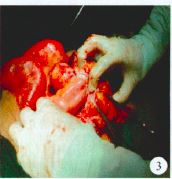

腹部立卧位X线平片提示:左中下腹小肠积气,结肠内较多粪便及气体。腹部超声检查:可见肠管样回声杂乱;见密集点状增强及减弱回声,提示腹部嵌顿疝可能性大。腹部CT检查显示:下腹壁巨大囊性包块,其中可见肠管扩张,肠绊扭曲(图2)。

图 2 下腹部 CT( 局部)显示:下腹壁巨大囊性包块,其中可见肠管扩张,肠绊扭曲